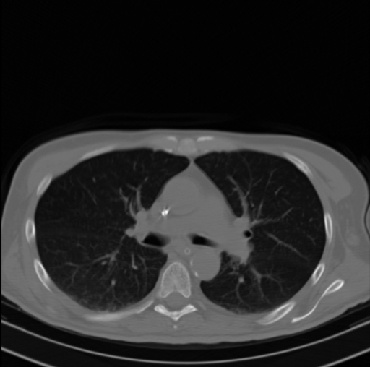

Early and reliable COVID-19 diagnosis based on chest 3-D CT scans can assist medical specialists in vital circumstances. Deep learning methodologies constitute a main approach for chest CT scan analysis and disease prediction. However, large annotated databases are necessary for developing deep learning models that are able to provide COVID-19 diagnosis across various medical environments in different countries. Due to privacy issues, publicly available COVID-19 CT datasets are highly difficult to obtain, which hinders the research and development of AI-enabled diagnosis methods of COVID-19 based on CT scans. In this paper we present the COV19-CT-DB database which is annotated for COVID-19, consisting of about 5,000 3-D CT scans, We have split the database in training, validation and test datasets. The former two datasets can be used for training and validation of machine learning models, while the latter will be used for evaluation of the developed models. We also present a deep learning approach, based on a CNN-RNN network and report its performance on the COVID19-CT-DB database.